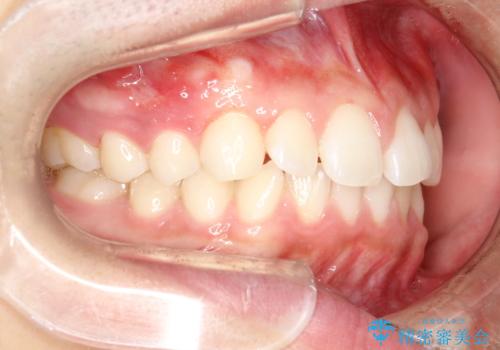

前歯の隙間がきになる インビザラインですきっ歯の治療

- 上の前歯の隙間を主訴に来院されました。

正中に隙間があり、かみ合わせが深い過蓋咬合という状態でした。

インビザラインにて矯正治療を行いました。

しっかり使っていただけたので、スムーズに治療を終了することができました。